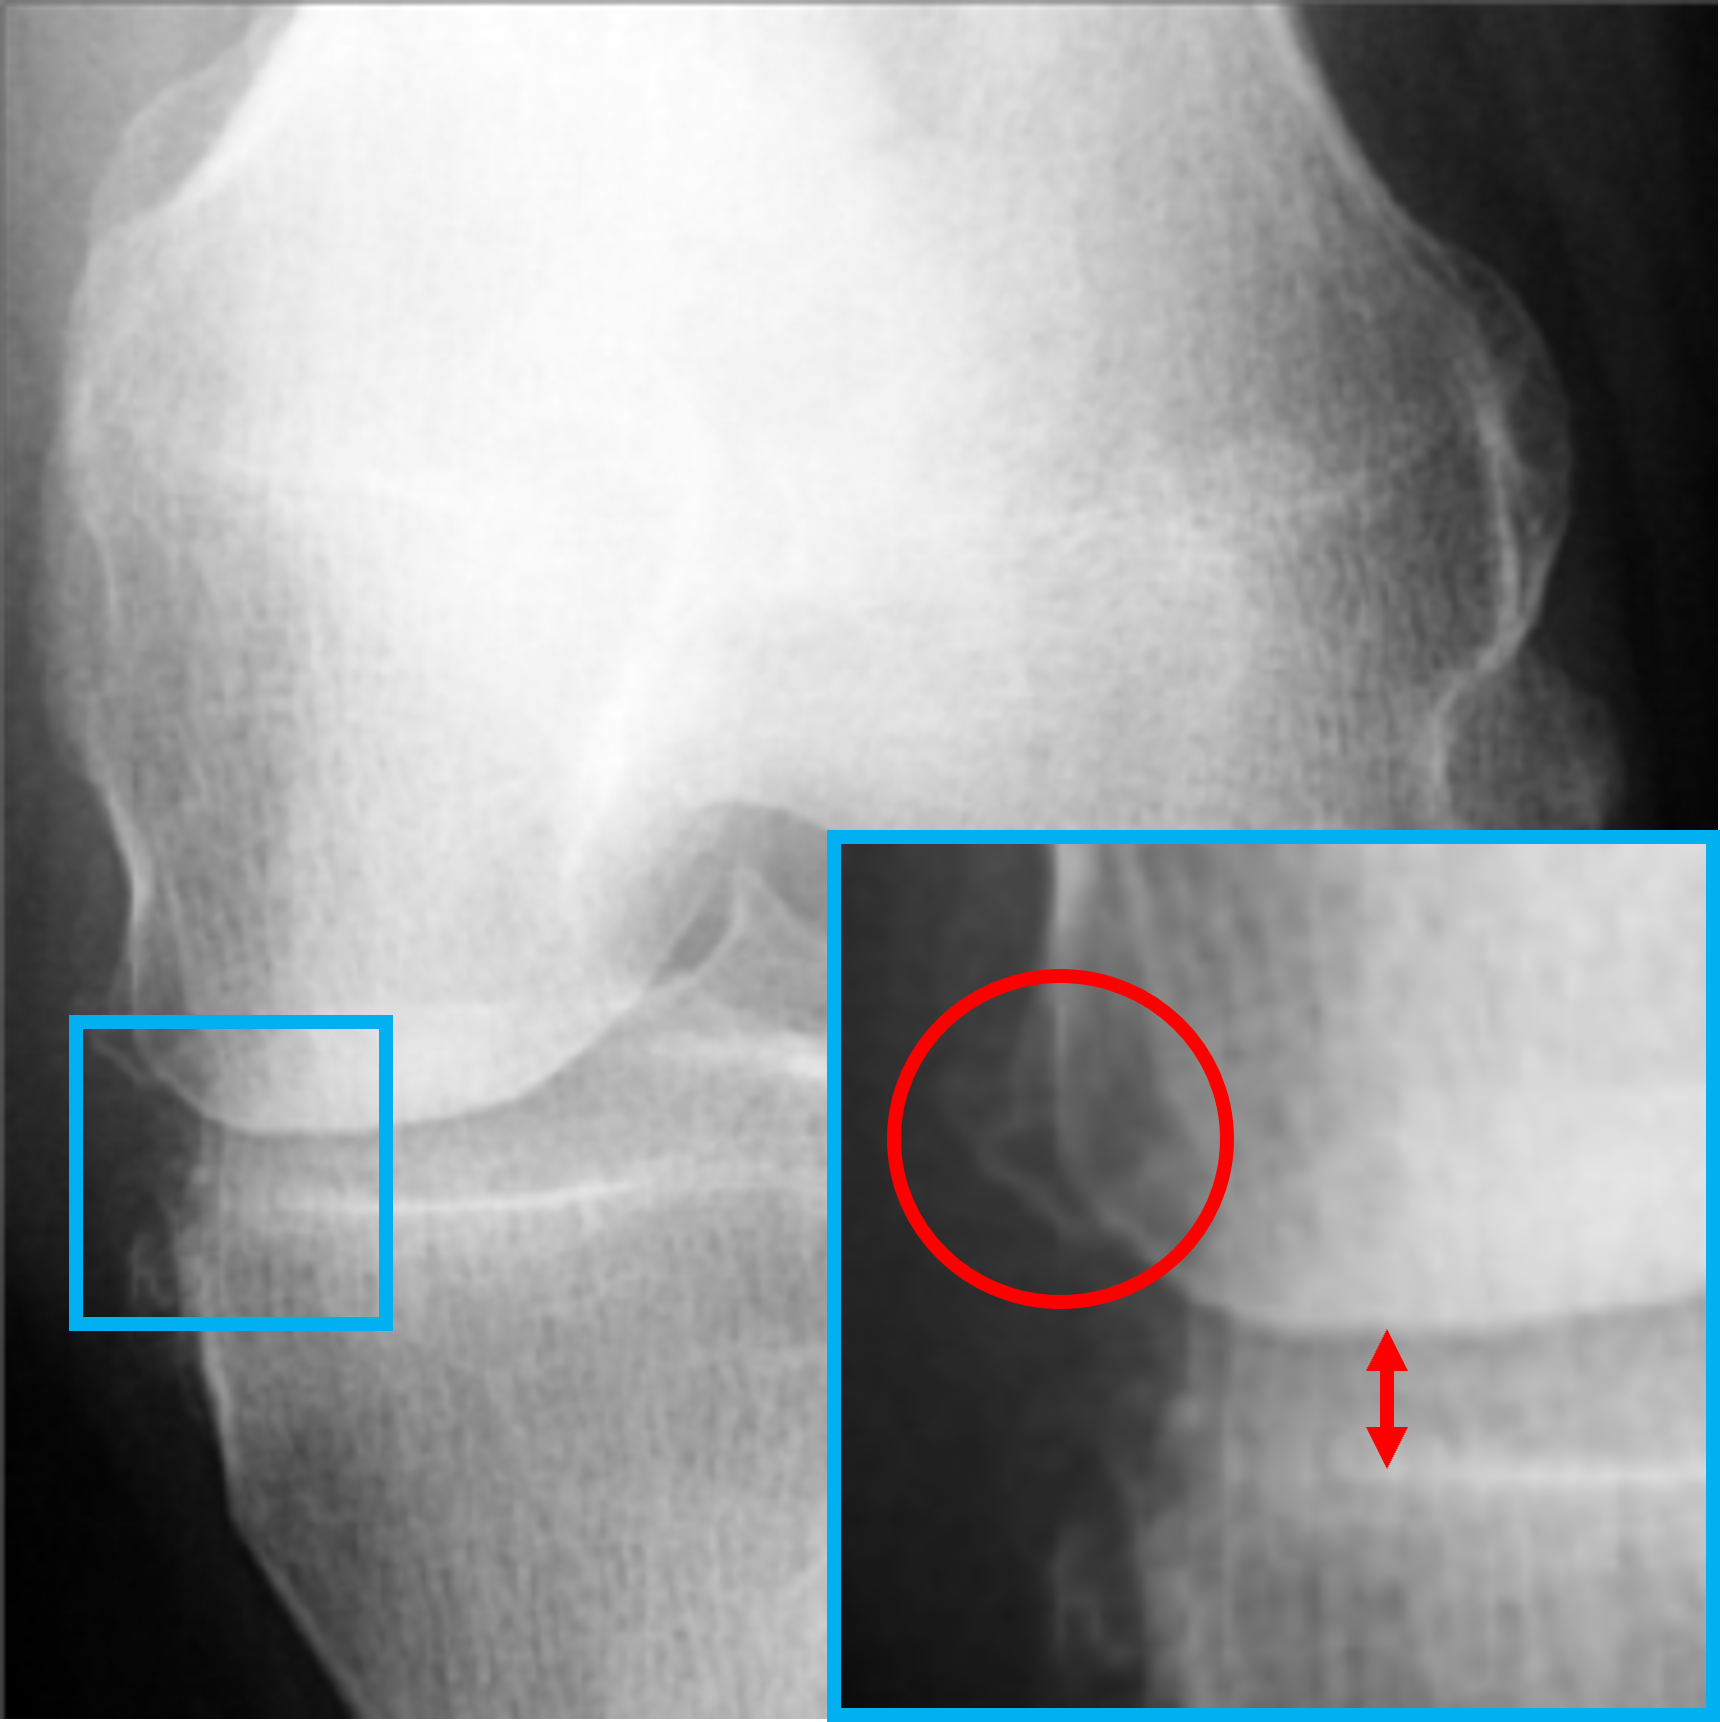

V-B Visualization of the feature vectors

To provide a more intuitive understanding of the proposed key feature exchange mechanism, we visualized the original inputs and their key-exchanged counterparts, as shown in Fig. 4. Specifically, X1subscript𝑋1X_{1}italic_X start_POSTSUBSCRIPT 1 end_POSTSUBSCRIPT (Fig. 4a), a KL-0 healthy knee X-ray, is contrasted with its key-exchanged output X1superscriptsubscript𝑋1X_{1}^{\prime}italic_X start_POSTSUBSCRIPT 1 end_POSTSUBSCRIPT start_POSTSUPERSCRIPT ′ end_POSTSUPERSCRIPT (Fig. 4b), while X2subscript𝑋2X_{2}italic_X start_POSTSUBSCRIPT 2 end_POSTSUBSCRIPT (Fig. 4c), a KL-2 osteoarthritic knee X-ray, is compared with X2superscriptsubscript𝑋2X_{2}^{\prime}italic_X start_POSTSUBSCRIPT 2 end_POSTSUBSCRIPT start_POSTSUPERSCRIPT ′ end_POSTSUPERSCRIPT (Fig. 4d). In X1subscriptsuperscript𝑋1X^{\prime}_{1}italic_X start_POSTSUPERSCRIPT ′ end_POSTSUPERSCRIPT start_POSTSUBSCRIPT 1 end_POSTSUBSCRIPT, pathological features associated with KL-2, JSN and osteophytes, are successfully introduced, while in X2subscriptsuperscript𝑋2X^{\prime}_{2}italic_X start_POSTSUPERSCRIPT ′ end_POSTSUPERSCRIPT start_POSTSUBSCRIPT 2 end_POSTSUBSCRIPT, these features are removed, restoring the joint space to resemble a healthy knee. It is noteworthy that, both X1subscriptsuperscript𝑋1X^{\prime}_{1}italic_X start_POSTSUPERSCRIPT ′ end_POSTSUPERSCRIPT start_POSTSUBSCRIPT 1 end_POSTSUBSCRIPT and X2subscriptsuperscript𝑋2X^{\prime}_{2}italic_X start_POSTSUPERSCRIPT ′ end_POSTSUPERSCRIPT start_POSTSUBSCRIPT 2 end_POSTSUBSCRIPT preserve the structural integrity and background details of the original images, demonstrating the model’s ability to selectively extract and modify key features without compromising realism. These visual results validate the effectiveness of our proposed global approach in separating key and non-key features, ensuring that the generated outputs are both diverse and valid. More details about the clinical validation will be discussed in Section V-E.

Refer to caption

(a) Original input X1subscript𝑋1X_{1}italic_X start_POSTSUBSCRIPT 1 end_POSTSUBSCRIPT (KL-0)

(b) key-exchanged output X1superscriptsubscript𝑋1X_{1}^{\prime}italic_X start_POSTSUBSCRIPT 1 end_POSTSUBSCRIPT start_POSTSUPERSCRIPT ′ end_POSTSUPERSCRIPT (KL-2)

(c) Original input X2subscript𝑋2X_{2}italic_X start_POSTSUBSCRIPT 2 end_POSTSUBSCRIPT (KL-2)

(d) Key-exchanged output X2superscriptsubscript𝑋2X_{2}^{\prime}italic_X start_POSTSUBSCRIPT 2 end_POSTSUBSCRIPT start_POSTSUPERSCRIPT ′ end_POSTSUPERSCRIPT (KL-0)

Figure 4: Highlighted illustration of the original inputs and key-exchanged outputs. The green and red colours represent the absence and presence of symptoms for osteophytes and JSN, respectively. The circles and arrows represent the possible positions of the osteophytes and JSN modification, respectively.